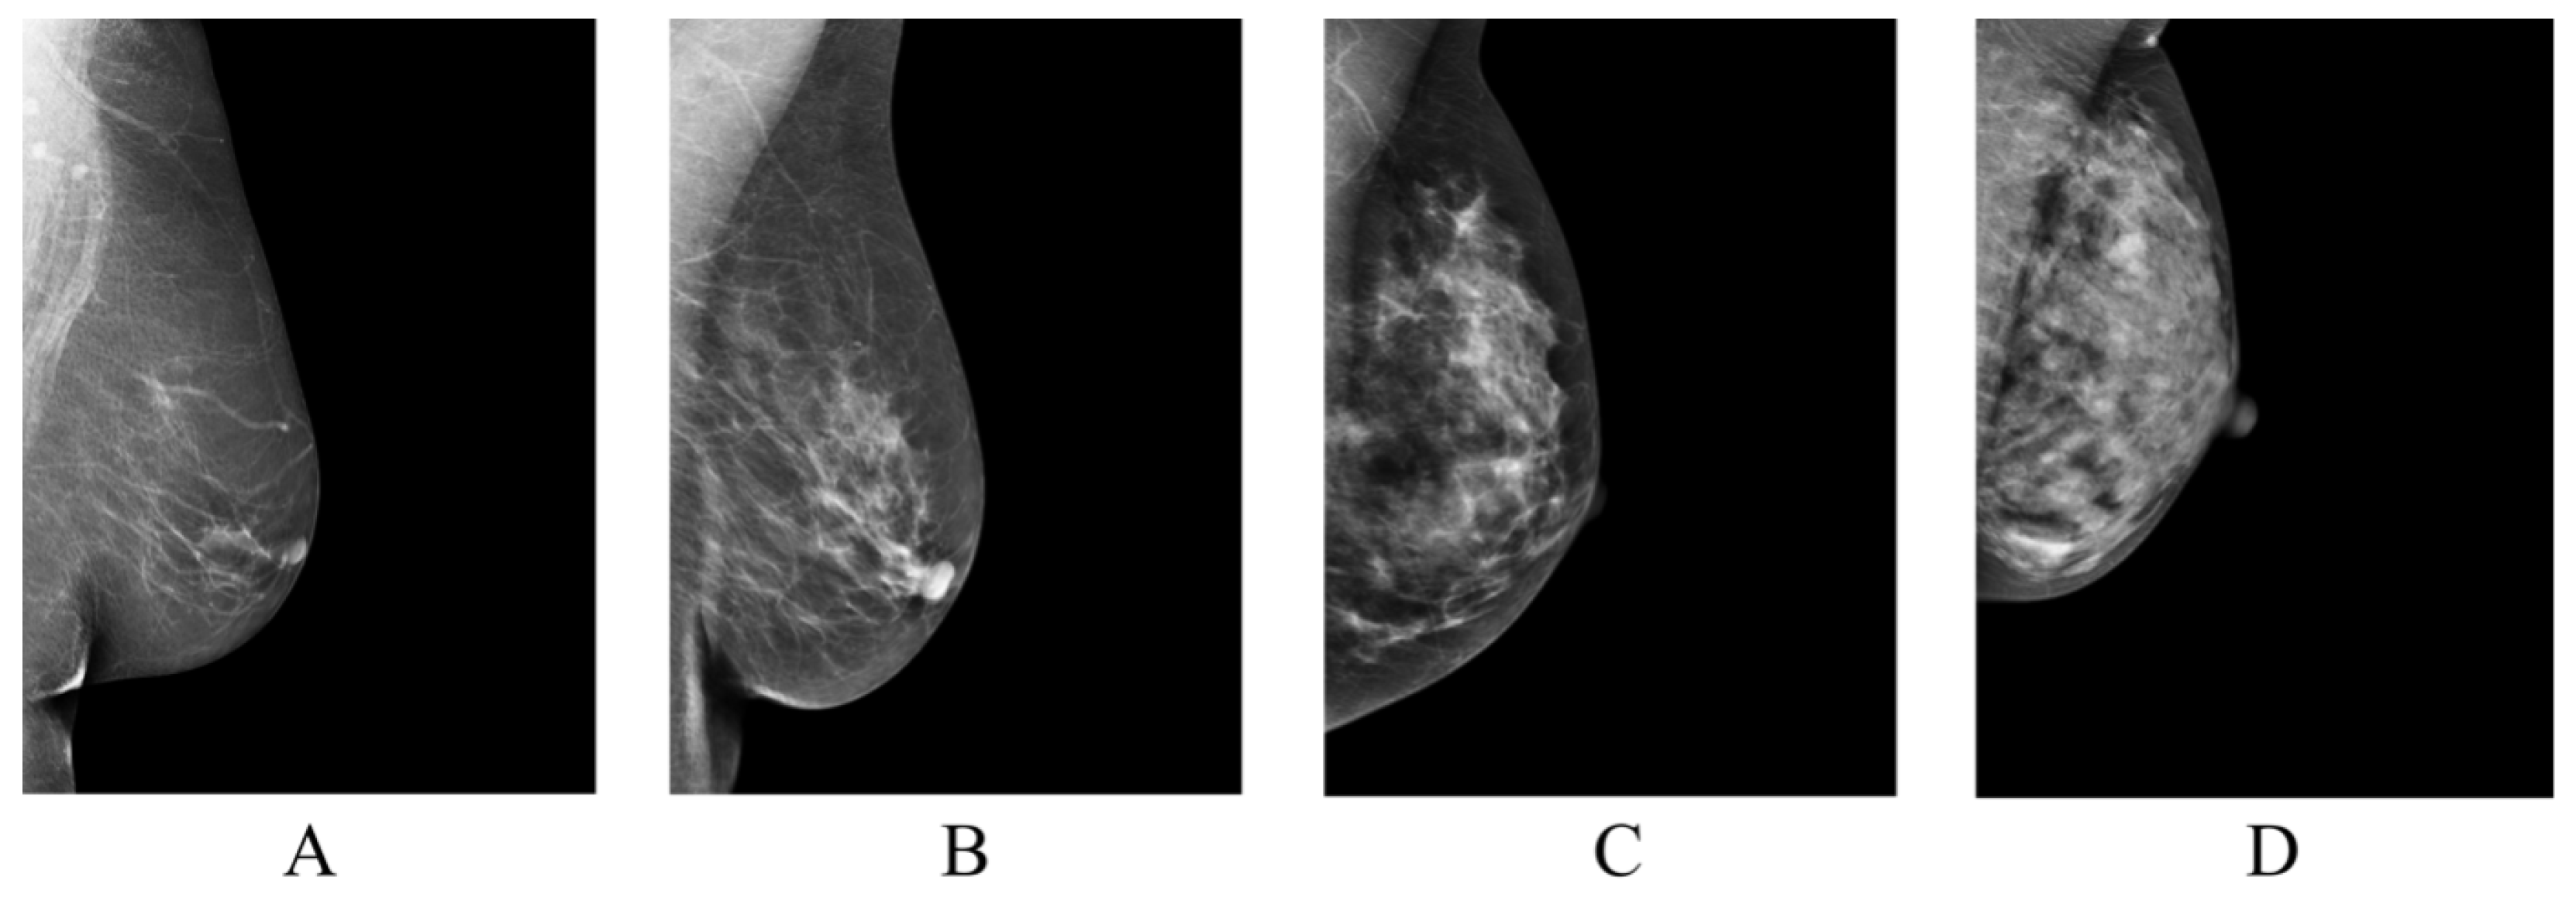

| BI-RADS Category | / |

|---|---|

| Class A | 879/3516 |

| Class B | 3212/12,848 |

| Class C | 928/3712 |

| Class D | 111/444 |

| Total | 5130/20,520 |

| Class A | 18/72 |

| Class B | 43/172 |

| Class C | 7/28 |

| Class D | 4/16 |

| Total | 72/288 |